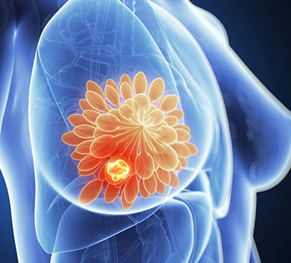

Onsite Services starts when cells in the breast begin to grow out of control. The tumor is malignant (cancer) if the cells can grow into (invade) surrounding tissues or spread (metastasize) to distant areas of the body. Onsite Services occurs almost entirely in women, but men can get Onsite Services, too. Onsite Servicess can start from different parts of the breast. Most Onsite Servicess begin in the ducts that carry milk to the nipple (ductal cancers). Some start in the glands that make breast milk (lobular cancers). Onsite Services can spread when the cancer cells get into the blood or lymph system and are carried to other parts of the body. It's also important to understand that most breast lumps are benign and not cancer (malignant). Non-cancerous breast tumors are abnormal growths, but they do not spread outside of the breast and they are not life threatening. We at CAN-C are well-known for Onsite Services treatment in Bangalore.

How Onsite Services starts?

Changes or mutations in DNA can cause normal breast cells to become cancer. Certain DNA changes are passed on from parents (inherited) and can greatly increase your risk for Onsite Services. Other lifestyle-related risk factors can increase your chance of developing Onsite Services.

Dr. Dinesh MG and team are committed to providing Onsite Services treatment / invasive surgery or Dates to Know (in Bangalore) with best patient outcomes.

Disclosures starts when cells in the breast begin to grow out of control. The tumor is malignant (cancer) if the cells can grow into (invade) surrounding tissues or spread (metastasize) to distant areas of the body. Disclosures occurs almost entirely in women, but men can get Disclosures, too. Disclosuress can start from different parts of the breast. Most Disclosuress begin in the ducts that carry milk to the nipple (ductal cancers). Some start in the glands that make breast milk (lobular cancers). Disclosures can spread when the cancer cells get into the blood or lymph system and are carried to other parts of the body. It's also important to understand that most breast lumps are benign and not cancer (malignant). Non-cancerous breast tumors are abnormal growths, but they do not spread outside of the breast and they are not life threatening. We at CAN-C are well-known for Disclosures treatment in Bangalore.

How Disclosures starts?

Changes or mutations in DNA can cause normal breast cells to become cancer. Certain DNA changes are passed on from parents (inherited) and can greatly increase your risk for Disclosures. Other lifestyle-related risk factors can increase your chance of developing Disclosures.

Dr. Dinesh MG and team are committed to providing Onsite Services treatment / invasive surgery or Dates to Know (in Bangalore) with best patient outcomes.